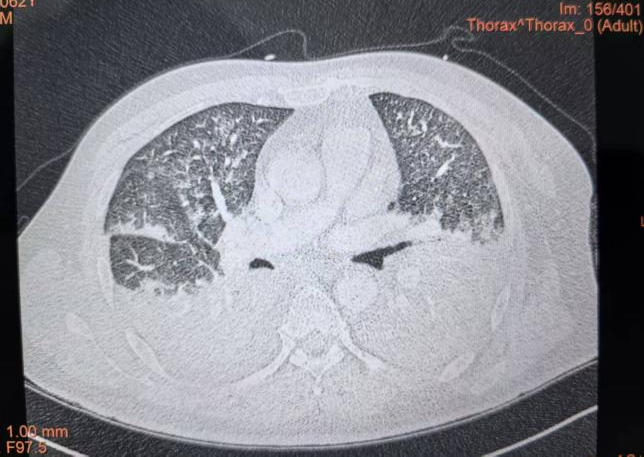

另一典型案例是一位脑出血后一周突发喘息伴低氧血症的患者。在常规复查血管彩超发现下肢深静脉血栓形成后,转运过程中突发喘息加重、血压下降、严重低氧。经紧急抢救,患者生命体征虽暂时稳定,但临床高度怀疑肺栓塞。紧急完善胸部强化CT检查,确诊肺栓塞,完善EIT监测显示:图像显示患者左侧肺部区域出现特征性的通气减低及阻抗异常改变,提示局部通气-灌注失衡,这与肺栓塞表现高度吻合。

确诊后,患者接受了抽栓及肝素持续泵入抗凝治疗。随着病情好转,复查EIT显示左侧通气血流ROI上升,胸部强化CT肺栓塞也较前好转。